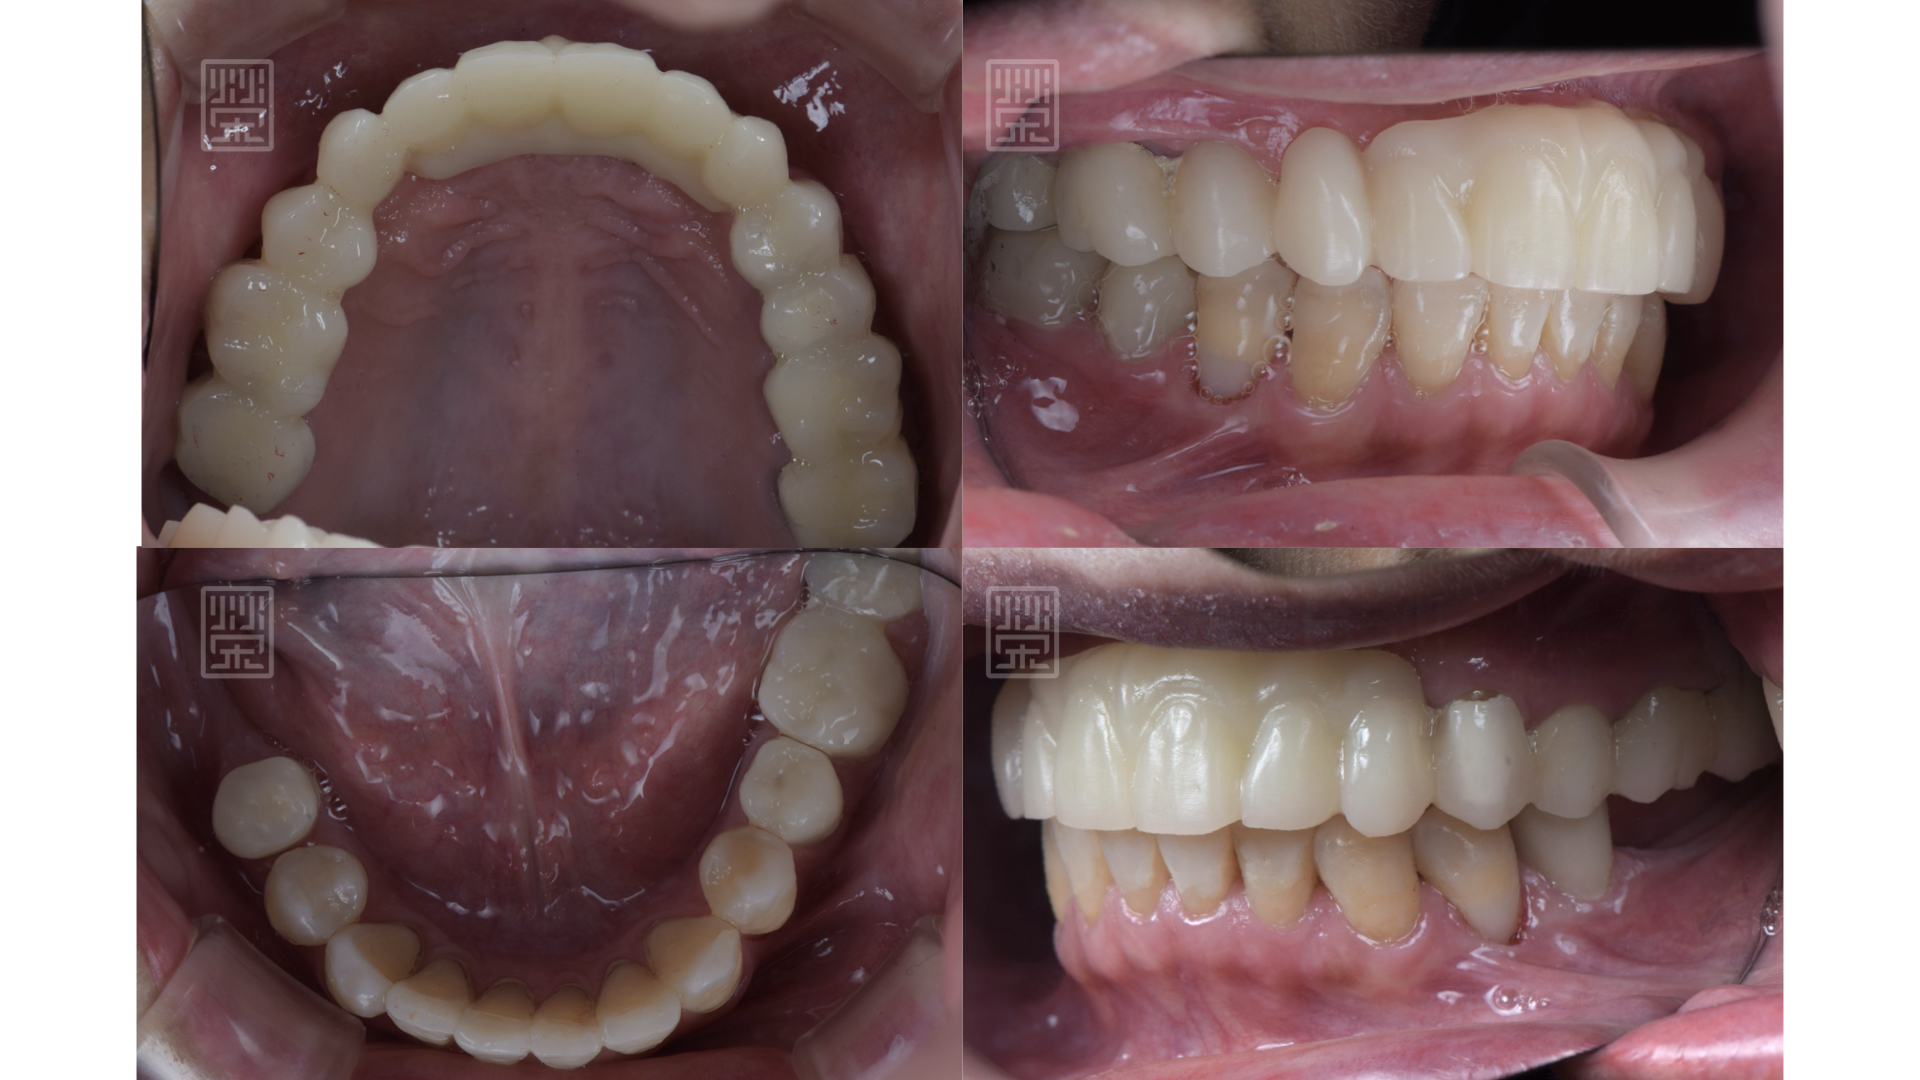

矯正後,再將門牙拉長,達到理想的牙齒的長度

適當分配牙齒導引位置,保護前後牙

用全瓷牙橋與牙齦色陶瓷,恢復牙齒外觀與型態

玻璃陶瓷貼片改變下顎門齒顏色與型態

全瓷贋復物完成

適當的咬合分配

藉由臨時假牙、矯正、更新臨時假牙,讓型態、長度、唇形充分瞭解與溝通

自信開朗的笑容